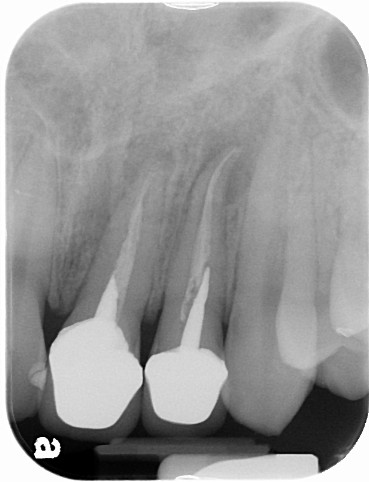

利用顯微鏡將金屬釘柱移除,再以鎳鈦超彈性器械修形根管(圖三),待患者的症狀都恢復正常後再利用熱塑型馬來膠將根管緻密封填(圖四),圖五為根管治療後的情況,與圖二相比,可見正門齒及側門齒已徹底封填。

圖十四為手術後的X光片,可見根尖逆充填及根尖囊腫,都已完全處理,經過6個月後,牙根的破壞已完全癒合(圖十五),可繼續進行瓷牙重建。